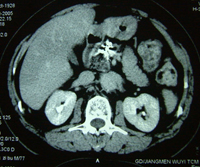

黄先生告诉记者:2004年7月初,他大便次数增多,腹部隐隐不适,去江门市人民医院检查,做B超和CT,发现胰腺肿癌。突然的打击几乎让他精神崩溃。黄先生的太太是护士,对胰腺癌的严重性早有所闻。有医生劝黄先生接受手术,但全家反对,一方面黄先生年事已高,另一方面他们了解胰腺癌能切除者微乎其微。一位邻居告诉他们:广州复大肿瘤医院有不开刀的冷冻治疗,对肝癌、肺癌等许多肿瘤有良好效果。7月14日,夫妻俩带着简单的行李,直奔广州,当日住进复大肿瘤医院。牛立志博士等医务人员给黄先生作了详细检查,作了肿瘤活检,确诊为胰腺囊腺癌。7月16日,黄先生接受了冷冻加125-碘粒子植入治疗。医生在CT引导下,作腹部穿刺,不开刀,将细针直接插入胰腺肿瘤内,先冷冻,再植入125碘粒子20粒。第二天,黄先生下地行走;第三天,恢复正常饮食;第八天,出院回家。三年来,除腿关节有点老年退化性变性外,他生活完全正常,无疼痛,食欲好,睡得香,每天散步半小时。CT复查显示:胰内肿瘤消失。

黄先生胰腺癌治疗前后CT:A 治疗前,B 治疗后3个月,C 治疗后 12个月